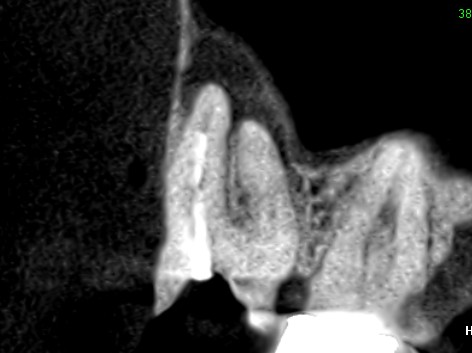

初診時のCT画像です。根管治療不足で根管充填が根の先まで足りていません。